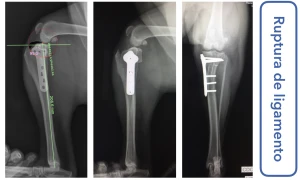

Sou médico veterinário especializado em ortopedia e cirurgias complexas em cães, com atuação em Ribeirão Preto. Realizo procedimentos como cirurgia de ligamento cruzado (TPLO), correção de luxação de patela e tratamento de fraturas, sempre com foco na recuperação funcional e qualidade de vida do paciente.

• Cirurgia de joelho, patela e fraturas em cães